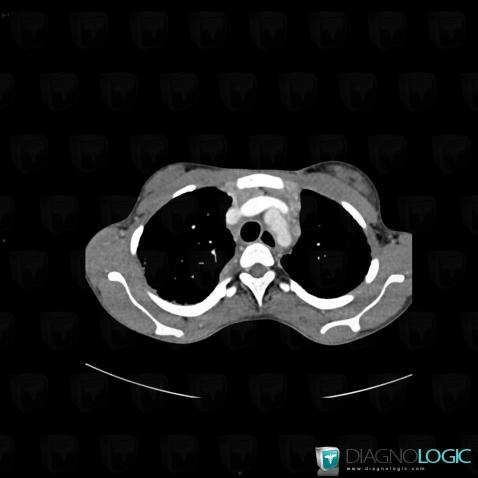

Sarcoïdose, Médiastin, Scanner

Voici les informations spécifiques à l'image clé ci dessus:

- Diagnostic Sarcoïdose, Localisation(s) Médiastin, comportant les gammes Masse médiastinale supérieure